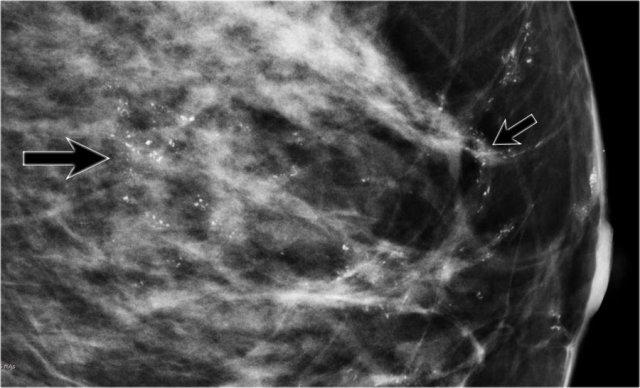

Có nhiều vôi hóa nhỏ, dạng tuyến tính phân bố trên một vùng rộng lớn của vú. Đây là các vôi hóa nghi ngờ và thường gặp trong DCIS. Nhấp để phóng to

80% trường hợp DCIS được chẩn đoán chỉ dựa trên nhũ ảnh thông qua hình ảnh vi vôi hóa (hình minh họa), tiếp theo là sinh thiết hút chân không. Rất ít trường hợp DCIS biểu hiện dưới dạng khối sờ thấy được.

Các phát hiện bao gồm:

- Nhiều vôi hóa nghi ngờ phân bố trên một vùng phân thùy rộng lớn của vú.

- Nhiều cụm vôi hóa – phần lớn có dạng phân nhánh tuyến tính – điển hình cho DCIS.

Do diện tích vùng vôi hóa rộng, phẫu thuật cắt bỏ tuyến vú đã được lên kế hoạch.

Thủ thuật hạch cửa cũng được thực hiện do kích thước ước tính của DCIS.

Khi có kế hoạch cắt bỏ tuyến vú, thủ thuật hạch cửa (SN) được thực hiện thường quy đồng thời, vì không thể tiến hành sau đó.

Kết quả giải phẫu bệnh cho thấy các ổ nhỏ ung thư xâm lấn.

Ở bệnh nhân này, có hai nhóm vôi hóa nghi ngờ cách nhau khoảng 5 cm.

Đầu tiên, nhóm vôi hóa lớn hơn được tiến hành sinh thiết.

Lý do là nếu các vôi hóa này là lành tính, thì cụm nhỏ hơn cũng có khả năng lành tính.

Tuy nhiên, nhóm vôi hóa lớn hơn được xác định là DCIS độ 2.

Do đó, cần tiến hành sinh thiết lần hai đối với nhóm vôi hóa nhỏ hơn, và kết quả cũng là DCIS độ 2.

Phẫu thuật cắt bỏ tuyến vú kết hợp thủ thuật hạch cửa đã được lên kế hoạch.

Tổng diện tích DCIS được đánh giá là quá rộng để có thể áp dụng điều trị bảo tồn vú.